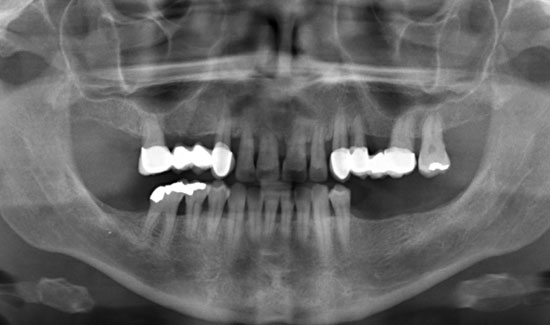

Fig. 2: Clinical aspect of region 12, formation of gas bubbles on the inflamed tissue. Continuous suction in the vicinity of the area of use

As an ozone gas source, we used Prozone, which, with the aid of plastic attachments, makes it possible to introduce ozone gas into the pockets in a pain-free manner. The local application of ozone gas was repeated three times, at weekly intervals. The patient was also made aware of necessary personal hygiene measures. Not only were we able to stop the bleeding, but we were also able to keep the degree of mobility of the teeth at a stable level (2) and reduce the measurable depth of the pockets.